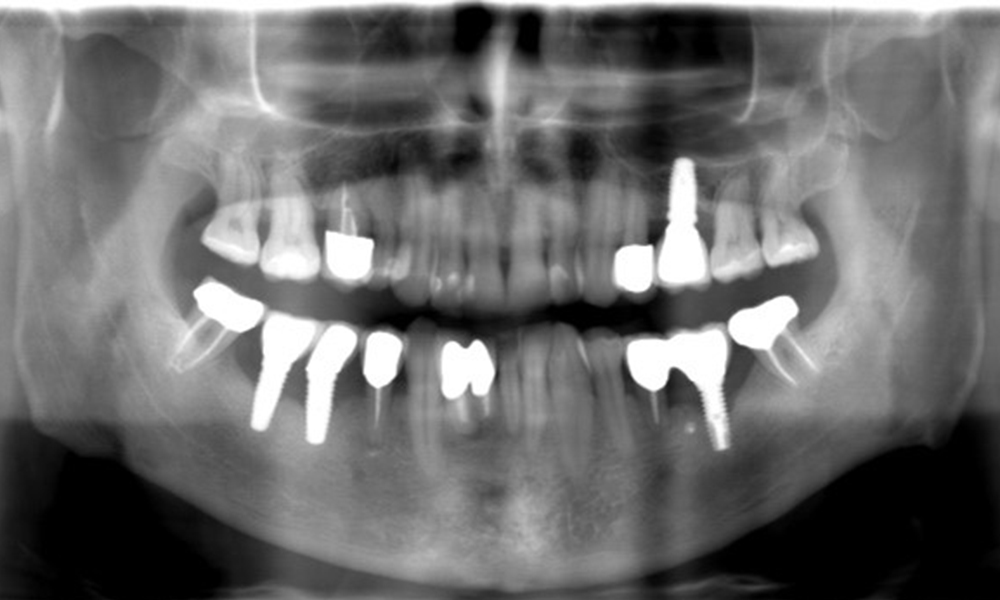

"Die Röntgenaufnahmen zeigen den Verlauf des Knochenabbaus. OPG vom 29.06.2020 (links) und OPG vom 26.02.2024 (rechts)

OPG: 26.02.2024 ZF: 18.01.2024